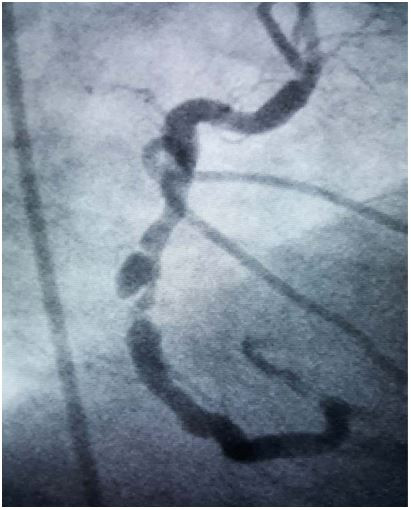

Observando a coronariografia abaixo de um paciente que se apresentou com síndrome coronariana aguda e marcadores de necrose miocárdica positivos, qual a artéria apresentada e o que a imagem representa?